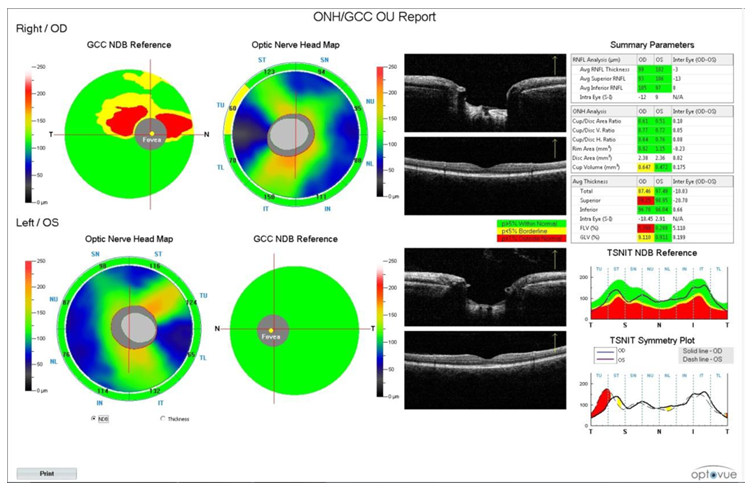

Cihazın makula değerlendirme programı ganglion hücre kompleksi (GCC) analizidir. Analiz edilen makula katları RSLT, RGH, IPL’dir ve bu üç katın toplam kalınlığını verir. Resim 7’de cihazın GCC çıktısı görülmektedir. Çıktının sol üst kısmında foveanın 1 mm temporalini merkez alan 7 mm2 alanda GCC haritası bulunur. Kalın alanlar sarı-turuncu; ince alanlar mavi-yeşil izlenir. Normatif veritabanı referans haritasında kırmızı alanlar anormal, sarı alanlar sınırda, yeşil alanlar normal olan bölgeleri gösterir. Foveada RGH olmadığından gri gösterilir. B-tarama görüntüleri, normatif veritabanı referans planındaki kırmızı çizgilerdeki kesitlerdir.

Renk kodlu kalınlık ve hacim parametre tablosunda ortalama, superior ve inferior GCC kalınlıkları yanısıra farklı iki parametre de yer alır: Fokal kayıp hacmi (FLV) ve global kayıp hacmi (GLV). FLV, görme alanındaki patern deviasyon haritası ile, GLV ise total deviasyon haritası ile karşılaştırılabilir. GLV, tüm GCC haritası boyunca GCC kaybının ortalama miktarını (%), yani diffüz kaybı; FLV ise anlamlı fokal kaybın olduğu yerde (Normal dağılımın 5. persantilinin altında) fraksiyonel sapmanın toplamı (%), yani fokal kaybı ölçer. GCC analizini spesifitesi ve sensitivitesini arttırırlar. GCC haritaları için de progresyon analizi mevcuttur.

Her iki gözün OSB/GCC analizlerini tek çıktıda görmek mümkündür. (Resim 8)

Resim 7: GCC analizi çıktısı

Resim 8: Her iki gözün OSB/GCC çıktısı